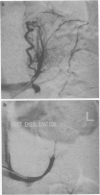

The management of a patient with severe Cushing's syndrome due to ectopic ACTH produced by a medullary carcinoma of the thyroid is described. Initial treatment with maximal adrenolytic medical therapy and two attempts at bilateral adrenal venous infarction had failed to control the disease, and she was at that time unfit for surgery. Subsequent use of bilateral adrenal arterial embolization enabled medical therapy to produce sufficient control of the Cushing's syndrome to allow bilateral adrenalectomy to be performed successfully, with resultant cure of the excessive cortisol production.